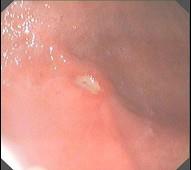

问题 男,34岁,4年来常出现右上腹痛,午夜尤甚,疼痛放射至背部,先后曾发生4次上消化道大出血,体检仅右上腹压痛。胃镜如图。以下最有可能的是 ( )

选项 A、胃溃疡 B、胃粘膜脱垂 C、慢性胃炎 D、十二指肠球后溃疡 E、胃癌

答案 D